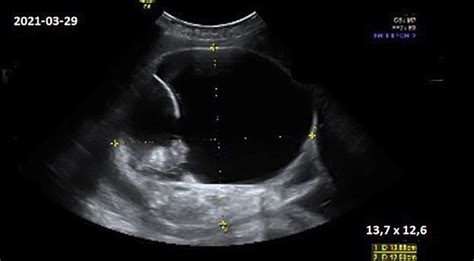

31 savaitę smegenys ir toliau vystosi, jos didėja. Pradeda aktyviai veikti nervų galūnės, formuojasi neuronų jungtys. Vaikas gali reaguoti į išorės garsus, gali parodyti nepasitenkinimą arba atvirkščiai - mėgti klausytis tam tikros muzikos. Svarbiausia, kad ji neskambėtų per garsiai, nes tai gali jį išgąsdinti. Kūdikis pradeda atskirti Jūsų ir tėvelio balsus. Jis taip pat reaguoja į šviesą. Tačiau kol kas jis neskiria spalvų, šis sugebėjimas išsivystys tik po kelių mėnesių po gimimo. Didelę įtaką turi ir Jūsų emocijos, jis supranta kada jaučiatės blogai, o kada laiminga. Per tyrimą ultragarsu galite pamatyti, ką vaikas veikia. Gana įdomu stebėti, kaip vaikas žaidžia su virkštele ar savo pirštais, uždengia veidą rankomis. Vaikelis jau pasiekė 41 centimetrą ir sveria maždaug 1,45 kilogramo. Šiuo metu nuo veido nuslenka smulkūs plaukeliai, kurie šildė kūną. Vystosi ir vaiko atmintis. Nuo šio mėnesio pabaigos, jūsų kūdikis sveria tarp 1,3 kg ir toliau sparčiai didės jo svoris, nes jo organizmas pradeda kaupti riebalų sankaupas. Vaisius jau puikiai gali matyti ir girdėti. Dauguma organizmo sistemų yra jau puikiai susiformavę. Jis gali pasukti į galvą žemyn ir po truputi jau keisti savo poziciją ir rengtis gimdymui. Jūsų mažylis dabar miega reguliariais laikotarpiais todėl turėtumėte pajusti jo judrumo ir ramybės laikus.

Svoris apie 2000-2200 g, ilgis apie 42-44 cm, beveik kaip gūžinė salota „Iceberg“! Smegenys ir nervų sistema jau išsivysčiusios, vaisius ima kurti savo imuninę sistemą. Oda tampa vis mažiau raukšlėta dėl po oda esančių baltųjų riebalų. Veido oda nebe tokia raudona, vis dar apaugusi gyvaplaukiais. Vaisiaus smegenys apsuptos plokščiais kaukolės kaulais, kurie dar nesuaugę. Vaisiaus būklė nuolat stebima, kad nebūtų užspausta virkštelė ar paliesta placenta. Kai artėjant gimdymui vaisius vis dar yra kojinėje pirmeigėjė padėtyje, gydytojas gali bandyti iš išorės apsukti kūdikį galva į priekį. Jis laiko rankas ant motinos pilvo ir, vadovaudamasis ultragarso vaizdu, stengiasi švelniai pakeisti vaisiaus padėtį. Procedūra atliekama prieš sąrėmius arba vos tik jiems pradidėjus. Dauguma vaisių taip ir lieka apsisukę galvyte žemyn, bet kai kurie ima vėl apsisuka į kojinę pirmeigę padėtį. Vaisiau padėtis galvytė žemyn sumažina tikimybę, jog reikės atlikti cezario pjūvį. Šioje ultragarso nuotraukoje puikiai matoma kūdikio ausis, kuri dabar jau yra visiškai susiformavusi tiek iš išorės, tiek iš vidaus.